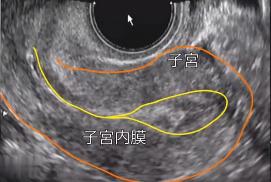

憋尿有个好处就是,可以形成一个透声窗,那么这时,医生在腹部B超的引导下,就可以很清楚看到子宫还有子宫内膜。